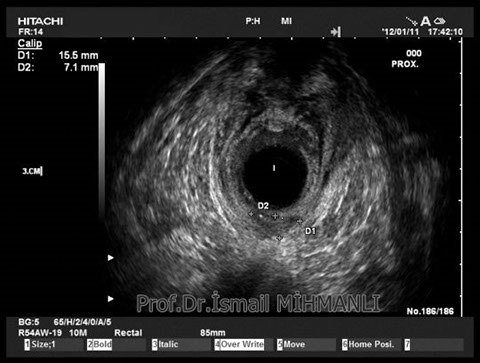

Transsfinkterik fistül

Fistüle makat kası hasarı eşlik ediyorsa endoanal US'de tespit edilir.